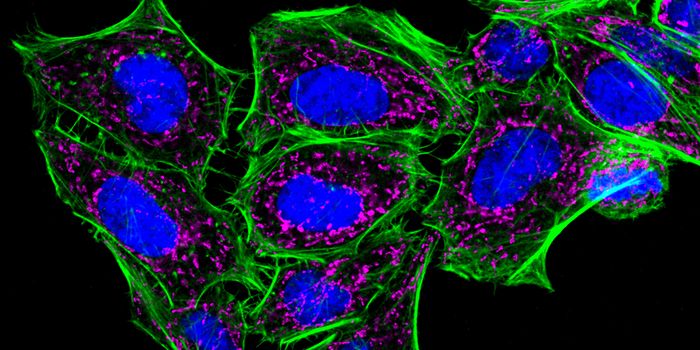

FEB 21, 2023Cell & Molecular BiologyThe Griffith Lab at UNC discovered telomeric protein & potential biomarker VR (green), shown in the nuclei (blue) of hum ...

AUG 31, 2021Clinical & Molecular DXCellular stains are organic fluorescent dyes or fluorescent conjugates designed to localize to a specific organelle or c ...